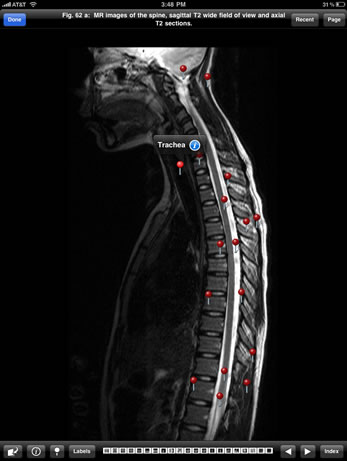

Preview the Imaging Atlas of Human Anatomy, featuring select images of the healthy human body as seen through a wide range of modern imaging techniques.

This Sampler is based on the print atlas, the Imaging Atlas of Human Anatomy, 4th Edition, written by Jamie Weir, Peter Abrahams, Jonathan D. Spratt, and Lonie Salkowski. The complete Atlas, also available in the modalityBODY Store, offers a comprehensive view of the structures and relationships within the body through a variety of imaging modalities.